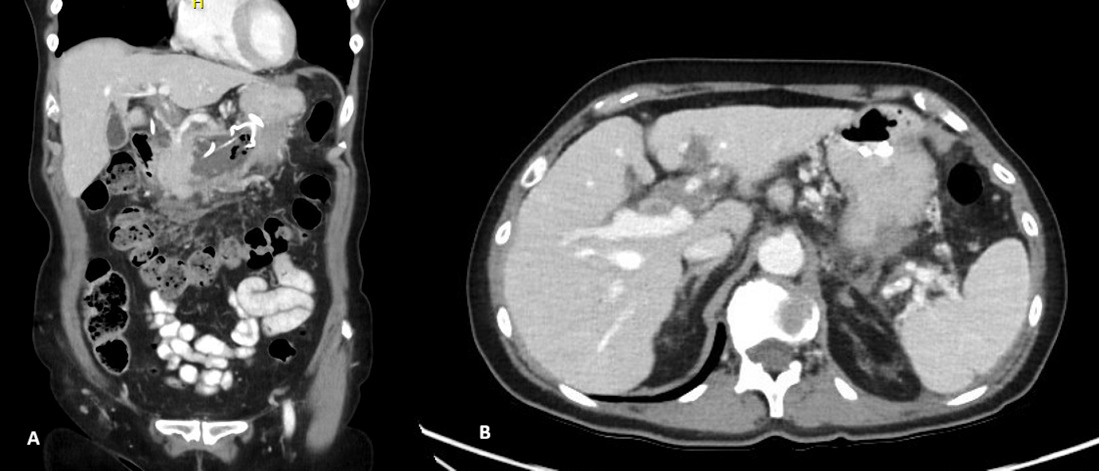

Despite biochemical improvement, the patient’s clinical course was complicated by persistent systemic inflammation and escalating abdominal pain. A contrast-enhanced computed tomography (CT) scan demonstrated features consistent with severe acute necrotizing pancreatitis, including extensive pancreatic oedema, areas of hypo-enhancement, marked peripancreatic fat stranding, and multiple peripancreatic fluid collections. The largest collection measured approximately 10 × 15 × 5 cm (Figure 1).

_and_axial_(b)_ct_scan_images_demonstrating_significant_pancreatic_necrosis_and.png)